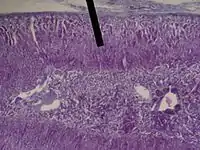

The zona fasciculata (sometimes, fascicular or fasiculate zone) constitutes the middle and also the widest zone of the adrenal cortex, sitting directly beneath the zona glomerulosa. Constituent cells are organized into bundles or "fascicles."

The zona fasciculata chiefly produces glucocorticoids (mainly cortisol in humans), which regulate the metabolism of glucose. Glucocorticoid production is stimulated by adrenocorticotropic hormone (ACTH), which is released from the anterior pituitary, especially in times of stress as part of the fight-or-flight response. The zona fasciculata also generates a small amount of weak androgens (e.g., dehydroepiandrosterone). The main source of androgens will come from the zona reticularis region. In certain animals such as rodents, the lack of 17alpha-hydroxylase results in the synthesis of corticosterone instead of cortisol.